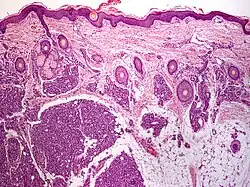

Imaging techniques such as magnetic resonance or ultrasound can be used to evaluate the affected area, distinguish one tumor from another, or both.[7] In the histopathology of tufted angioma, many lobules of tufts with a "cannonball" look are dispersed throughout the dermis, and crescent-shaped gaps are seen around the vascular tufts and in the tumor stroma.[3][10][11] In addition to CD31 and CD34, immunohistochemistry can be significantly positive for EN4 and Ulex uropaeus I lectin. It is sporadically positive for smooth muscle actin and negatively stained for GLUT.[11][7]